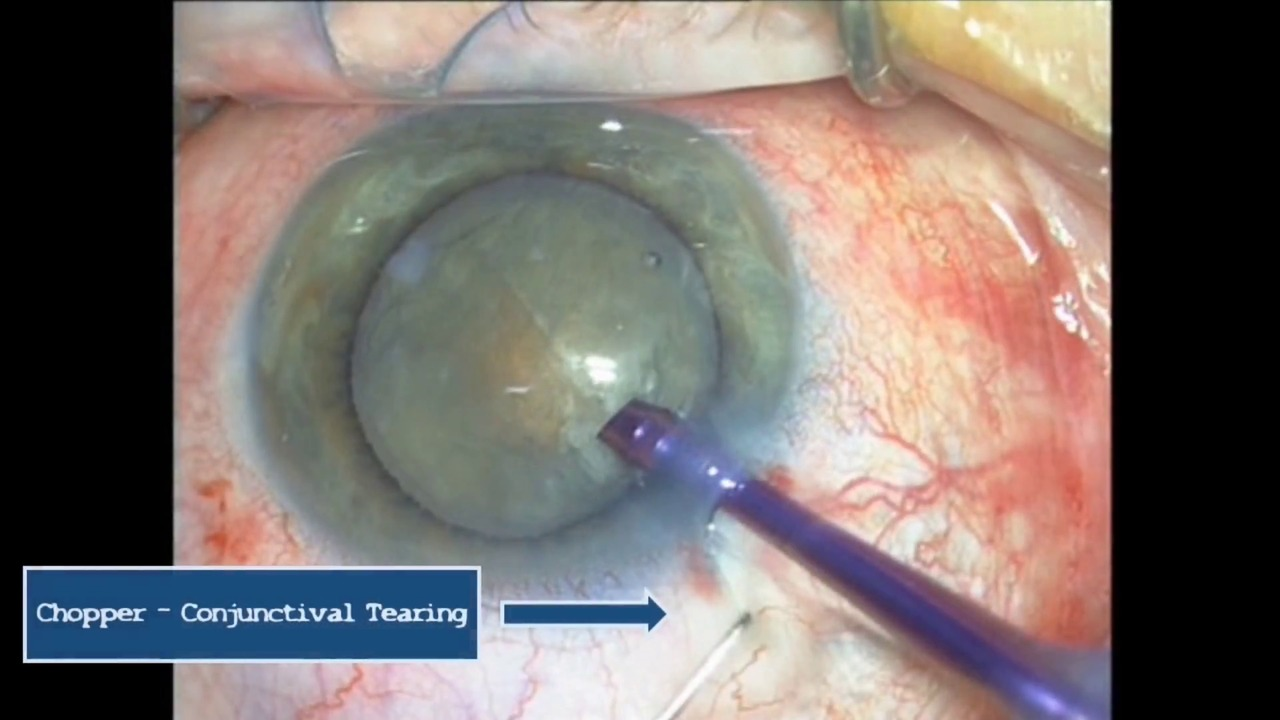

В нижченаведеному відео Anton Giulio Catania, MD, та Alessandro Galan, MD пропонують альтернативний хірургічний маневр, з використанням подрібнювача, без виймання факоемульсифікаційного, та іригаційного з аспіраційним наконечників з рогівкового розрізу. Кон’юнктивальна тканина зачіплюється біля лімбу, в тій самій точці, де рідина почала просочуватись під нею, відкриваючи цю точку, що забезпечує дренаж та попереджає подальшому накопиченню рідини. Швидкість виконання цих дій є обов’язковою, починаючи одразу після появи перших ознак набряку кон’юнктиви. Якщо виконати цю маніпуляцію вчасно, вона є ефективним та швидкодіючим маневром, який можна виконати без переривання процедури факоемульсифікації. Пацієнт не відчуває болю, навіть коли процедура проводиться під місцевою анестезією. Кровотеча зустрічається вкрай рідко.

Кон’юнктива швидко загоюється, і вже в перший післяопераційний день важко визначити місце, де була відкрита кон’юнктива.